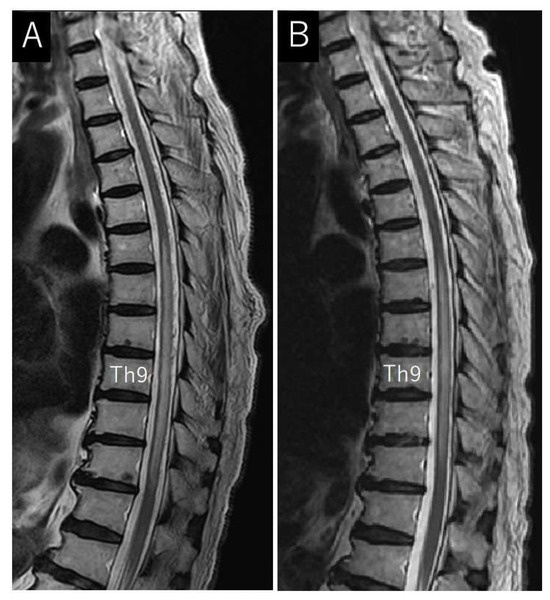

Case Description

4.5. Treatment and Outcomes